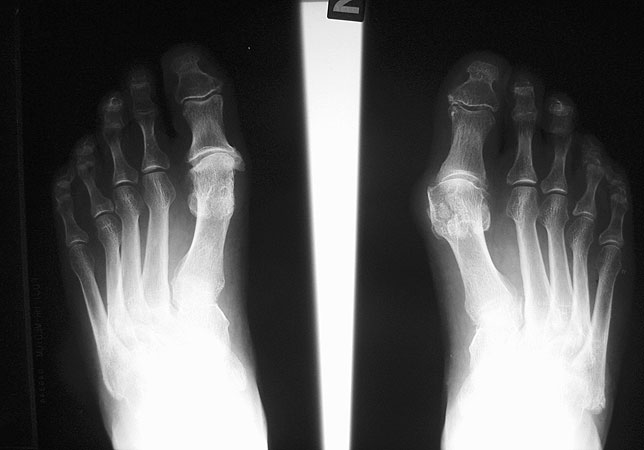

Röntgenbild 30 Jahre nach Brandes OP links zur OP Planung rechts.

Abbildung 6

Meine positive Einstellung gegenüber diesem Operationsverfahren stammt aus der Zeit meiner Promotion (Thomsen 1988) über die Ergebnisse nach Brandesoperation. Damals war diese Operation favorisiert für Patienten über 40 Jahre. Von den 244 Patienten mit 391 Brandesoperationen waren knapp 90 Prozent auch nach 10-15 Jahren noch mit dem funktionellen Ergebnis der Operation zufrieden, 83 % auch mit dem kosmetischen Ergebnis.

Generell ist die subjektive Zufriedenheit der Patienten mit dieser Operationstechnik aber sehr hoch und die Komplikations- und Revisionsrate auch nach langer Zeit  im Vergleich zu konkurrierenden Verfahren gering 14. Auch sehen wir unverändert Patienten die 20-30 Jahre nach Primäreingriff zufrieden zur Operation der Gegenseite kommen (Abb. 6)